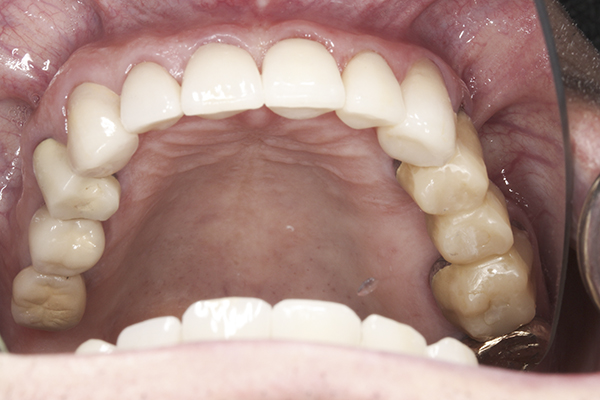

(41.) Postoperative maxillary occlusal view. Note the composite tops on teeth Nos. 12 through 14.

Figure 41

(42.) Postoperative mandibular occlusal view. Note the composite tops on teeth Nos. 28 through 31.

Figure 42